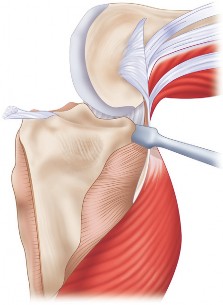

هذه الجراحة ليست مجرد استبدال للمفصل التالف، بل هي عملية تصحيحية شاملة تهدف إلى إعادة المحاذاة الطبيعية للركبة والتخلص من الانحراف التقوسي الذي يسبب الألم ويُسرّع من تدهور المفصل. بفضل الخبرة الواسعة للأستاذ الدكتور محمد هطيف التي تمتد لأكثر من عقدين من الزمن كأستاذ جامعي وجراح عظام متخصص، وباستخدامه لأحدث التقنيات الجراحية مثل الجراحة المجهرية وتنظير المفصل بتقنية 4K وزراعة المفاصل المتقدمة، يتمكن مرضى خشونة الركبة التقوسية في صنعاء من استعادة حركتهم الطبيعية والعيش بلا ألم.

تُغطى نهايات هذه العظام بغضروف مفصلي أملس ومرن (غضروف زجاجي)، يسمح للعظام بالانزلاق بسلاسة فوق بعضها البعض دون احتكاك، ويمتص الصدمات. يوجد أيضًا غضروفان هلاليان (Menisci) على شكل حرف C بين عظم الفخذ وعظم الساق، يعملان كممتصات صدمات إضافية ويزيدان من استقرار المفصل.

يُحاط المفصل بمحفظة مفصلية تحتوي على سائل زليلي (Synovial Fluid) يغذي الغضروف ويزيت المفصل. تُعزز استقرار الركبة بواسطة شبكة قوية من الأربطة:

- الأربطة الصليبية (Cruciate Ligaments): الأمامي والخلفي، يقعان داخل المفصل ويمنعان الانزلاق الأمامي والخلفي لعظم الساق.

- الأربطة الجانبية (Collateral Ligaments): الإنسي والوحشي، يقعان على جانبي المفصل ويوفران الاستقرار الجانبي.

تعمل العضلات المحيطة بالركبة، مثل العضلة الرباعية في الفخذ وعضلات أوتار الركبة، مع الأوتار على تحريك المفصل وتثبيته. أي خلل في هذه المكونات يمكن أن يؤدي إلى الألم، عدم الاستقرار، وتدهور وظيفة الركبة، وهو ما يحدث غالبًا في حالات خشونة الركبة التقوسية.